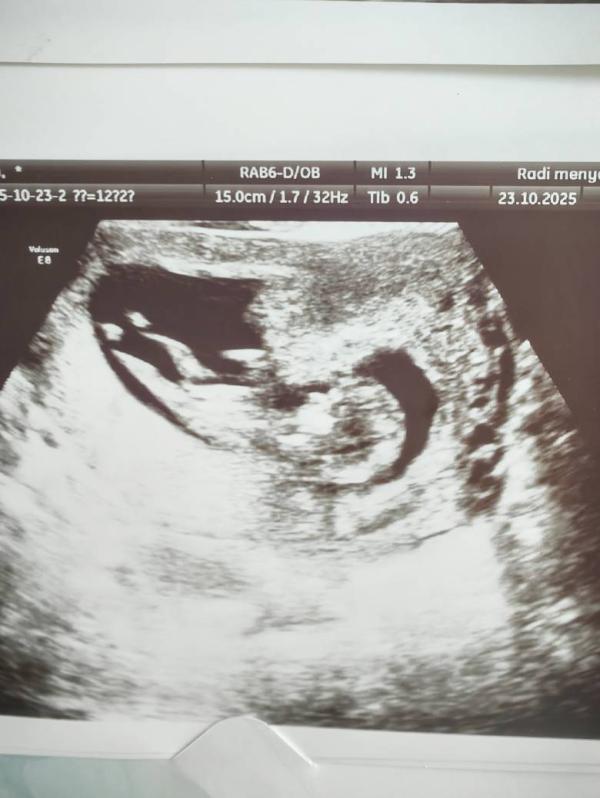

Девочки, покидайте свои фото с узи 12 недель, где видно пол 😄 нам сказали сбоку мальчик, снизу девочка

У младшего как будто похоже на наше фото, наверное опять мальчик 😅